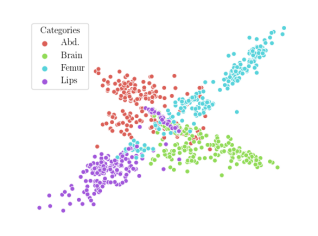

We compare the -distance of categorical features and domain features. Fig. 5 (a) shows that domain difference is higher in domain features than in categorical features. This indicates that domain features contain more domain information whereas categorical features are more domain-invariant. Fig. 6 shows the t-SNE plot of categorical features in both domains for MIDNet. From Fig. 6 (a), we observe that the categorical features learned by MIDNet enable the anatomical classification. Fig. 6 (b) shows that the learned categorical features are domain-invariant.

In addition, we utilize t-SNE plots for feature visualization in Fig. 10. Comparing Fig. 10 (a) and Fig. 10 (b), we observe that with mutual information disentanglement, (1) samples from the same category are more tightly clustered (see the top row) and (2) the source domain and the target domain are overlap more (see the bottom row). This indicates that mutual information disentanglement is important for learning categorical-focused and domain-invariant features. Fig. 10 (a), (c)-(d) show that the proposed method outperforms other state-of-the-art methods for learning category-discriminative and domain-invariant features, especially for unseen categories in the target domain (e.g., (a) vs. (d)).